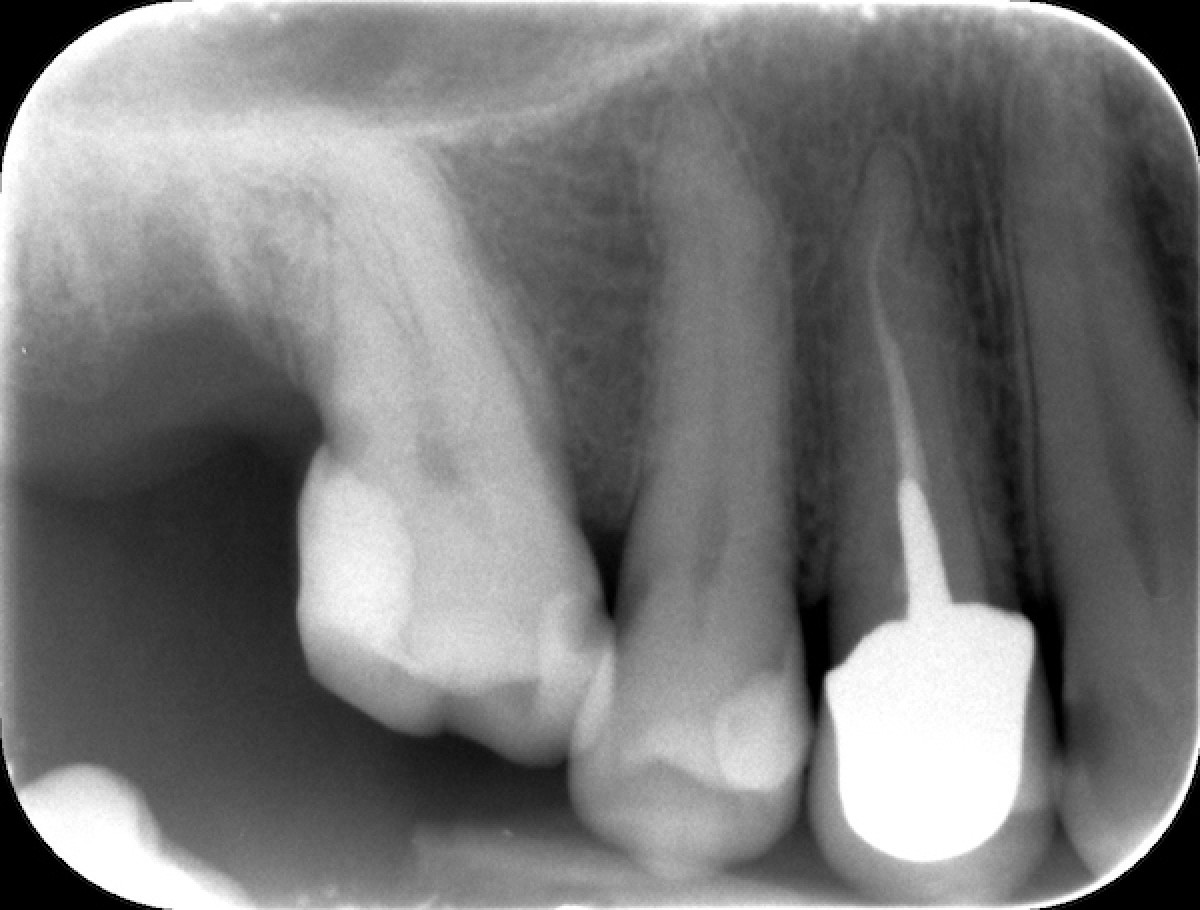

54 ys old male patient came with the complaint of pain and sensitivity in mandibular right first molar and endo-treatment was advised.

After accessing the pulp chamber and locating all the canal orifices, patency to length is confirmed with a stainless-steel manual file (0.10-0.15) and the Hyflex file sequence is selected in relation to the anatomical challenge encountered during manual scouting and the analysis of the preoperative x-ray  showed a complex and highly curved anatomy of the roots. The canal orifices were relocated using the Orifice Opener EDM In this case a 15.3 and a 20.5 were used to create a smooth mechanical glide path thanks to the great flexibility and cutting efficiency of the file. The distal canal was completed with the OneFile while in the palatal and mesio-buccal was not possible to reach WL with 25.8 EDM because of the curvature. Thus the sequence was completed with 25.4, 30.4, 35.4 from cm files sequence and 40.4 EDM file in both canals, according to the apical diameter gouging. Cold 5 % sodium hypochlorite was used throughout the procedure as the irrigant. Canals were dried with paper point and obturation was done by using single cones of taper and size corresponding to the ones of the last file used for shaping plus Gutta Flow Bioseal as cement. The tooth was restored with a composite overlay (figure 6,7).